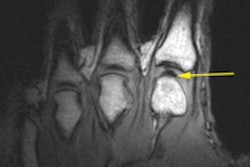

![]() |

| The two clinical images show the difference in a plain radiograph (above) and fluoroscopic image (below) of the same wrist and the modalities' ability to show the scapholunate interval. |

The 2-mm benchmark is important because if the scapholunate space, or interval, is greater than 2 mm, the wrist injury requires additional follow-up. "It doesn't automatically mean the scapholunate or the ligament is torn," Lahey said, "but if [the scapholunate space] is greater than 2 mm and it is different than the other side -- the contralateral wrist -- then it warrants further investigation and most likely is torn."